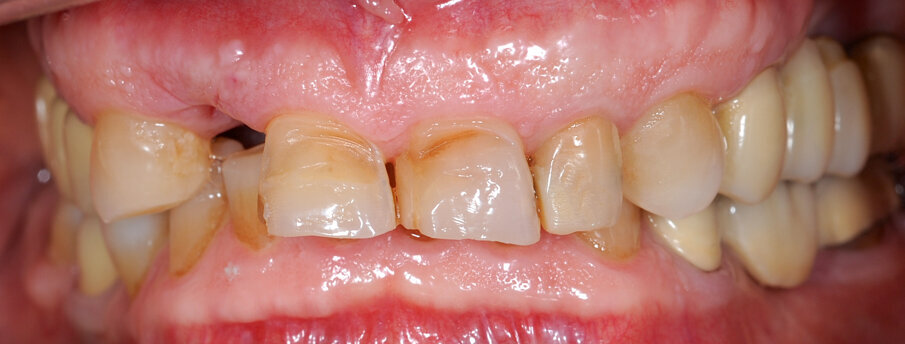

Un paziente di 66 anni, con anamnesi patologica di NIDDM ben compensato e cardio-vasculopatia ischemica in buon compenso farmacologico, si presenta alla nostra attenzione per ascesso parodontale alla radice residua del dente 1.2 e per multiple fratture dei manufatti protesici esistenti (Figg. 1-6). È evidente la presenza di grave malocclusione con perdita di VDO, usure e fratture dei restauri protesici e dei denti residui, presenza di abfractions cervicali. Il paziente evidenzia alla visita modesta dolenzia muscolare alla palpazione, specie a carico dei muscoli pterigoidei mediali e temporali, apertura della bocca ridotta e lieve rumorosità delle TMJ.

L’infezione a carico della radice del dente 1.2 è immediatamente attribuibile a frattura verticale con sondaggio positivo di 9 mm (Fig. 7). Estratta la radice di 1.2 fratturata, il paziente richiede una riabilitazione protesica fissa all’arcata superiore che preveda il minor numero possibile di interventi endodontici e chirurgici. Viene da noi proposta una riabilitazione protesica full arch che consenta, previo studio del caso gnatologico e terapia interlocutoria con provvisori in PMMA, la definizione di un’occlusione a funzione sequenziale in TRP per l’aumento controllato della VDO e la stabilizzazione dei rapporti articolari, ora visibilmente compromessi.